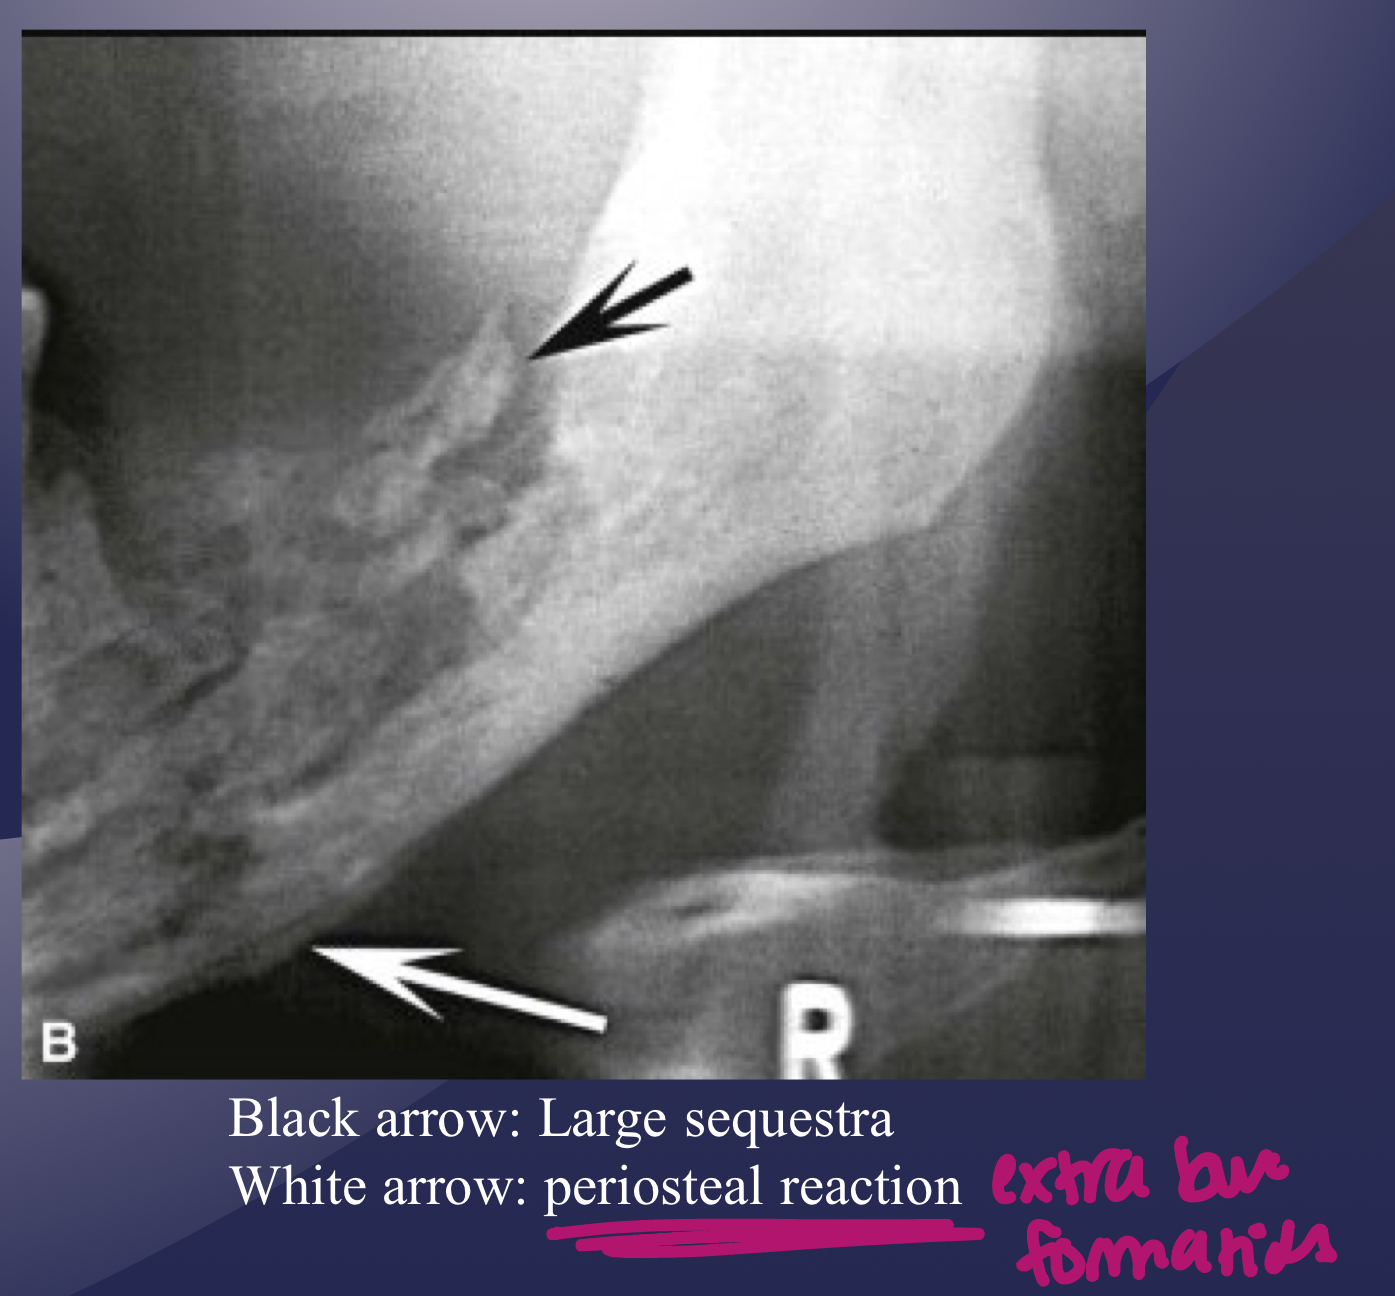

white and black arrow

which imaging is method of choice for seeing internal structure (sequestrea) of acute osteomyelitis?

periosteal reaction

new bone formation parallel to the cortex (almost looks like periosteum lifted and bone under)

proliferative periostitis and the onion skin periosteal reaction have the same radiographic appearance

true